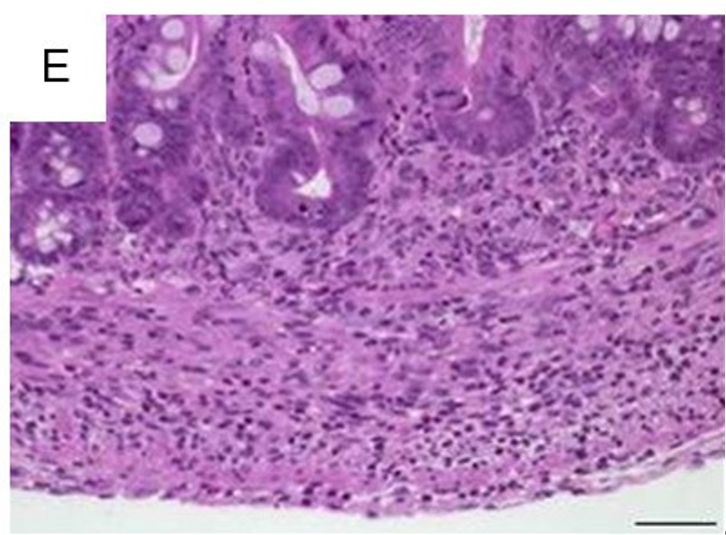

白细胞浸润固有层,这是所有肠炎模型的共有特征。尽管浸润了不同比例的嗜中性粒细胞、嗜酸性粒细胞、单核细胞、浆细胞和淋巴细胞,评估每高倍视野(HPF)组织内混合的炎症细胞,可充分反映了炎症相关的变化(图1A)。散在中性粒细胞是轻度浸润的典型特征(图1B)。从炎症细胞的主要局部粘膜定位开始(图1C),严重程度增加首先包括粘膜下层(图1D),随后延伸至固有肌层并最终导致透壁浸润(图1E)。最初见于上皮细胞层的主要变化包括隐窝上皮细胞增生,杯状细胞的损失,隐窝炎、隐窝脓肿和糜烂。

1(C)混合炎性细胞的多灶性粘膜浸润(箭头;×100,比例尺100µm)